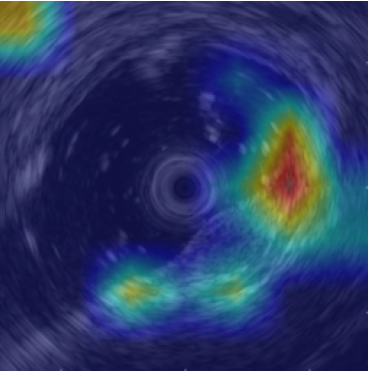

5.2 Visualization of attention weights

Fig. 5 presents a qualitative visualization of the learned word-to-region correspondences facilitated by our AGA framework. The top row shows the original medical images, including both chest X-rays (CXR) and endoscopic ultrasound (EUS) images. The bottom row displays the corresponding heatmaps generated by our model, where warmer colors denote higher activation weights, indicating stronger associations between specific image regions and the given medical concepts. For Atelectasis and Pneumonia, the model focuses on appropriate pulmonary regions, demonstrating strong localization aligned with radiological pathology. For the SMTs domain, terms like low-echoic mass and protruded into the cavity activate precisely the relevant interior structures of the lesion in EUS images. The distinct and interpretable activation patterns validate the effectiveness of our AGA mechanism in achieving fine-grained multimodal alignment.

low-echoic

mass

protruded

into the

cavity

clear

boundaries